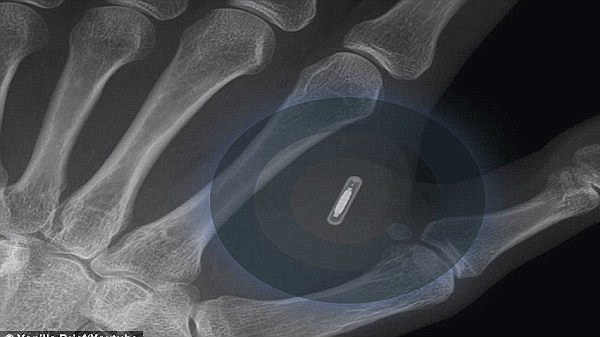

இப்போது வரும் பல்வேறு புதிய தொழில்நுட்பங்கள் நமக்கு மிகவும் உபயோகமாக இருக்கிறது, ஆனாலும் சில தீமைகளும் உள்ளது என்று தான் கூறவேண்டும். பயோசிப் என்பது சிம் கார்டு போன்று இருக்கும் மிகச் சிறிய எலக்ட்ரானிக் பொருள் ஆகும், குறிப்பாக இதனை உடலில் எந்தப் பகுதியிலும் பொறுத்திக் கொள்ள முடியும் என்று கூறப்படுகிறது.

இந்த பையோ சிப் பொறுத்திக்கொள்ள மருத்துவமணைகளில் சிறப்பு ஏற்பாடு செய்யப்பட்டிருந்தது, அதன்படி நிறுவனத்தின்

வேலை செய்யும் பணியாளர்களின் கைகளில் கட்டை விரலுக்கும், ஆள்காட்டி விரலுக்கும் இடையில் மருத்துவர்கள் பையோ சிப்-ஐ

பொருத்தினர் என்பது குறிப்பிடத்தக்கது.